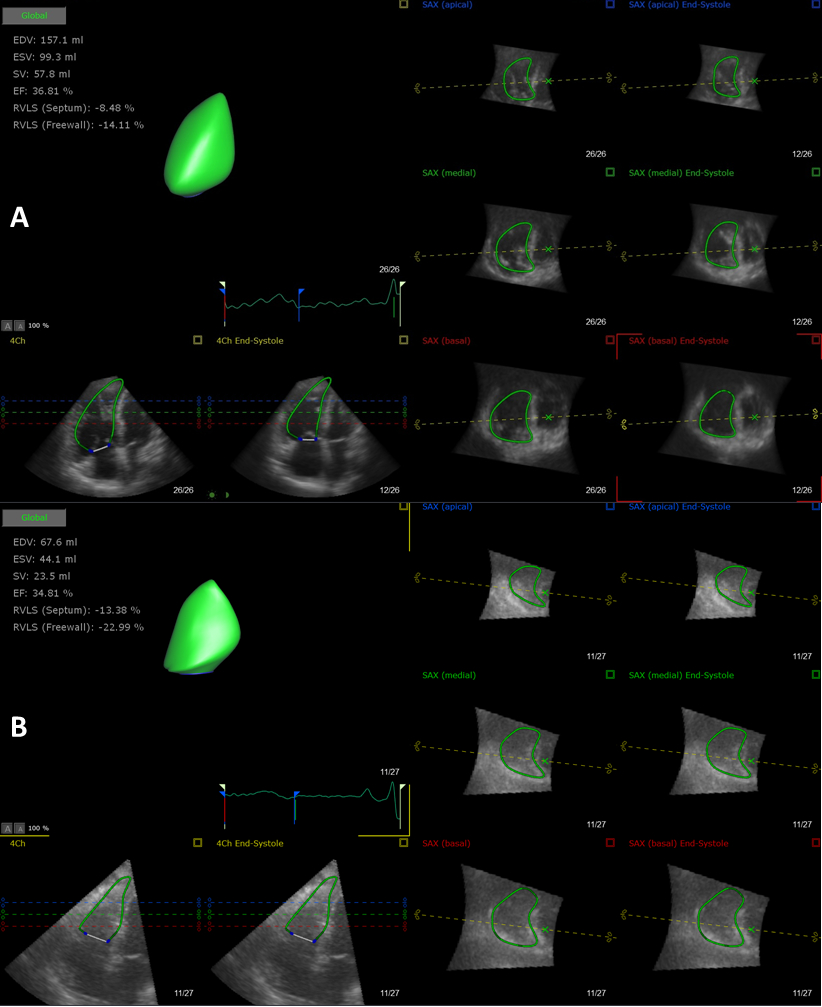

Methods: We prospectively enrolled PcPH patients from March 2017 to May 2018. 3DE sequences were analyzed by semi-automatic software (TomTec 4D RV-Function 2.0). RV end-diastolic volume (EDV), end-systolic volume (ESV), ejection fraction, longitudinal strain of septum and free wall, tricuspid annular plane systolic excursion were obtained. All participants were classified into low and intermediate-high risk groups based on 2015 ESC Guidelines. Patients were followed-up till May 2019 for death due to RV failure as an end-point.

Results: We finally enrolled 112 PcPH patients (average 36 years, 39 males and 73 females) in our study. Mean follow-up time was 18 months, and 11 patients died. Receive operating characteristic curves identified RV-3D-EDV=150ml and RV-3D-ESV=109ml as optimal cut-offs. Multivariate Cox proportional regression analyses indicated RV-3D-EDV>150ml and RV-3D-ESV>109ml were independent predictors of mortality after adjusted by age, gender, BMI or Risk stratification. McNemar-Bowker test revealed that compared with risk stratification, RV-3D-EDV>150ml (67.3% vs 44.6%, P <0.01) and RV-3D-ESV>109ml (62.4% vs 44.6%, P <0.01) had better predictive specificities for end-point.